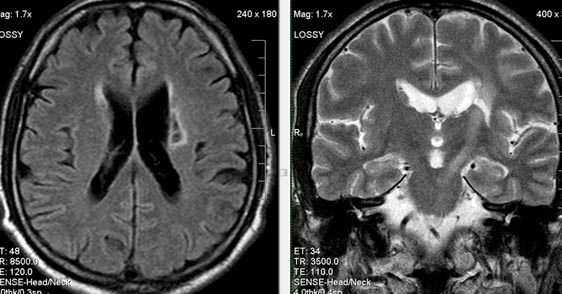

Лакунарное ишемическое ОНМК на фоне хронической сосудистой недостаточности.

Некоторые инфаркты при дисциркуляторной энцефалопатии протекают бессимптомно. Это «немые» инфаркты, которые, как правило, локализуются в глубоких отделах мозга и диагностируются только при МРТ. Этот случай показывает возможности выявление очага ограниченного ишемического ОНМК базальных ядер слева на фоне хронической ишемии.

Выраженная сосудистая энцефалопатия с наличием множественных очагов хронической ишемии, лакунарных постишемических кист. Программа ДВИ четко показывает фокус острого ОНМК в базальных ядрах справа на фоне лейкодистрофии.

Ишемической инсульт в бассейне левой средней мозговой артерии. Отсутствие феномена пустоты потока на уровне интракраниального отдела левой ВСА (признаки замедления кровотока).

Ишемический инсульт в ВББ слева. Отсутствие феномена пустоты потока на уровне экстракраниального отдела левой позвоночной артерии (признаки замедления кровотока).